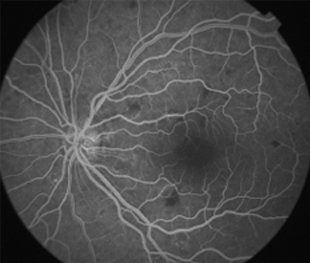

Angiografía OD

- Angiografía: teñido arterial, escape capilar, más tardíamente, no perfusion arteriolar y venular con teñido de las paredes vasculares y dilatación venosa.